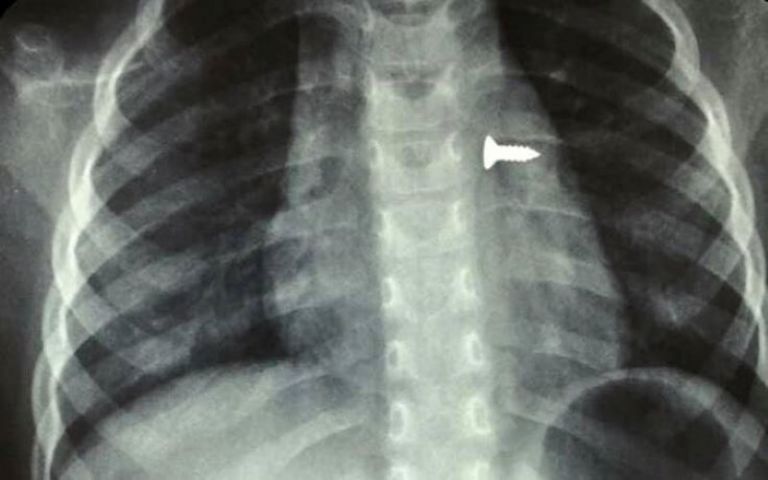

Σύμφωνα με τα όσα έκανε γνωστά ο αναπληρωτής καθηγητής ΩΡΛ της Ιατρικής Σχολής Κρήτης, Μανώλης Προκοπάκης, το κοριτσάκι μεταφέρθηκε στο νοσοκομείο και αμέσως του έγιναν ακτινογραφίες που έδειξαν πού βρισκόταν η βίδα.

Οι γιατροί άμεσα οδήγησαν τo τρίχρονο παιδί στο χειρουργείο και μετά από αρκετή ώρα κατάφεραν να αφαιρέσουν την βίδα. Ο κ. Προκοπάκης σε ανάρτησή του στα social media ανέφερε: «Πολύ επείγον χειρουργείο! Πριν από λίγο. Αφαίρεση βίδας από αριστερό βρογχικό δέντρο τρίχρονου κοριτσιού. Πολύ επικίνδυνο…».